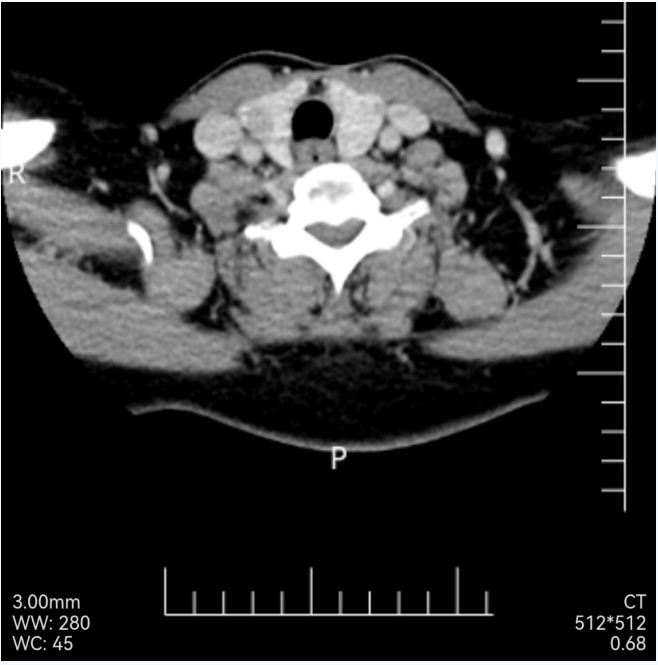

The outpatient department was admitted to the hospital with the diagnosis of "papillary carcinoma of the right thyroid". There was no obvious surgical contraindication after completing preoperative examination, and no abnormal enlarged lymph nodes were found in the neck by enhanced CT scanning.2

Neck enhanced CT showed that the right lobe of the thyroid occupied the middle pole, with a diameter of 1.1cm. Please consider the clinic. Multiple small lymph nodes can be seen on both sides of the neck without abnormal enhancement.